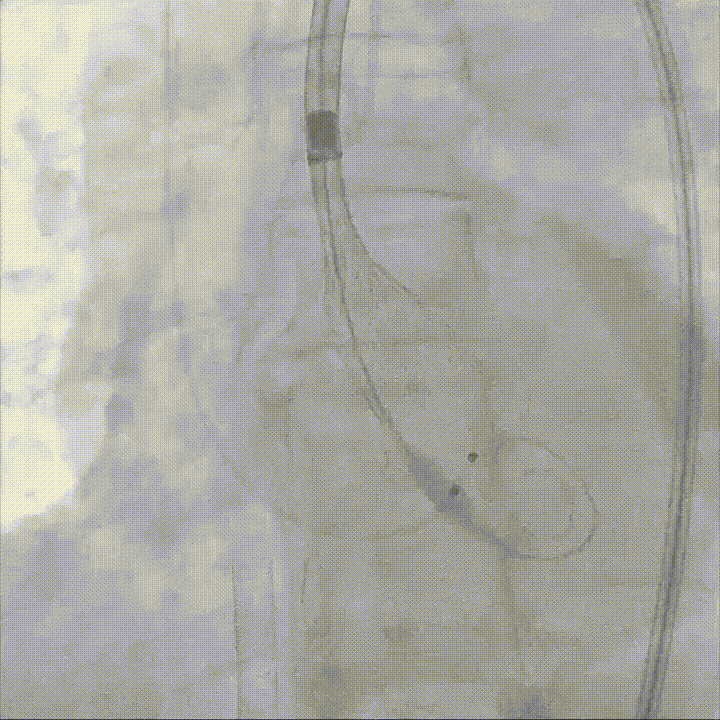

在保护右冠的前提下,精确释放开窗支架,恢复右冠灌注,随后行球囊后扩确保瓣膜贴壁充分,兼顾瓣膜功能与冠脉通畅;

右冠保护下球囊后扩

复查造影及食道超声示瓣膜位置,形态满意,瓣周漏较前明显好转,右冠血流恢复,无栓塞迹象;

术后造影